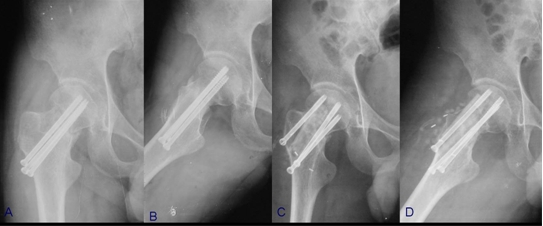

骨折端充分显露后,可直视下清理骨折端至新鲜断面,通过牵引、内旋下肢间接复位或撬拨骨折端直接复位,随后多枚克氏针临时固定,透视下见骨折端复位满意后进行最终的内固定,股骨颈骨折可采用多枚平行拉力螺钉或锁定钢板,同时行吻合血管的游离腓骨移植(图5),粗隆间骨折可根据其骨折类型选用锁定钢板或髓内钉,通常无需植骨(图6)。

图5 股骨颈骨不连病例

A,B,患者术前髋部正侧位片示股骨颈骨不连;C,D,患者术后髋部正侧位